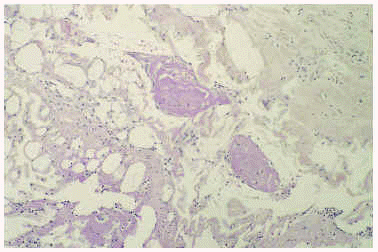

Un cultivo del exudado de una úlcera aisló Staphylococcus aureus, aunque el tratamiento antibiótico no modificó la evolución del cuadro. El estudio histopatológico de una lesión ulcerosa de reciente aparición, localizada en brazo, mostró una alteración en cuña con una úlcera superficial acompañada de un denso infiltrado inflamatorio difuso en el área superficial constituido por linfocitos, histiocitos y neutrófilos. En el vértice de la cuña, situado en la unión dermohipodérmica, se apreciaba una arteriola que contenía un trombo de fibrina que ocluía por completo la luz (fig. 2). A ese nivel se observaban escasas células inflamatorias sin relación con el vaso. Alrededor de la úlcera, se observaban diversas alteraciones en los vasos sanguíneos. Algunos vasos de la dermis mostraban una luz dilatada con una pared engrosada que contenía un material hialino (fig. 3), mientras que otros presentaban una luz estrecha con una pared rodeada de fibrina, muchos de ellos con trombos intraluminales.

Fig 3.--Caso 1. Vaso dilatado con un material hialino en la pared. Este vaso estaba localizado en la dermis papilar, por fuera de la úlcera con una epidermis suprayacente normal.